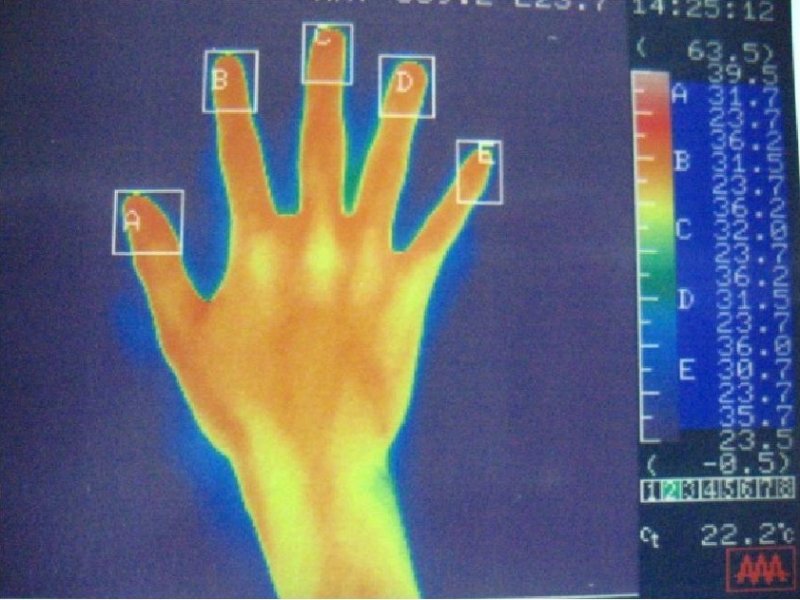

サーモグラフィー

左手

右手

赤い部分が高温部位を示しています。

左手

右手

明らかに両手の体温の低下がみられ、術直後から多汗症の症状は消失します。